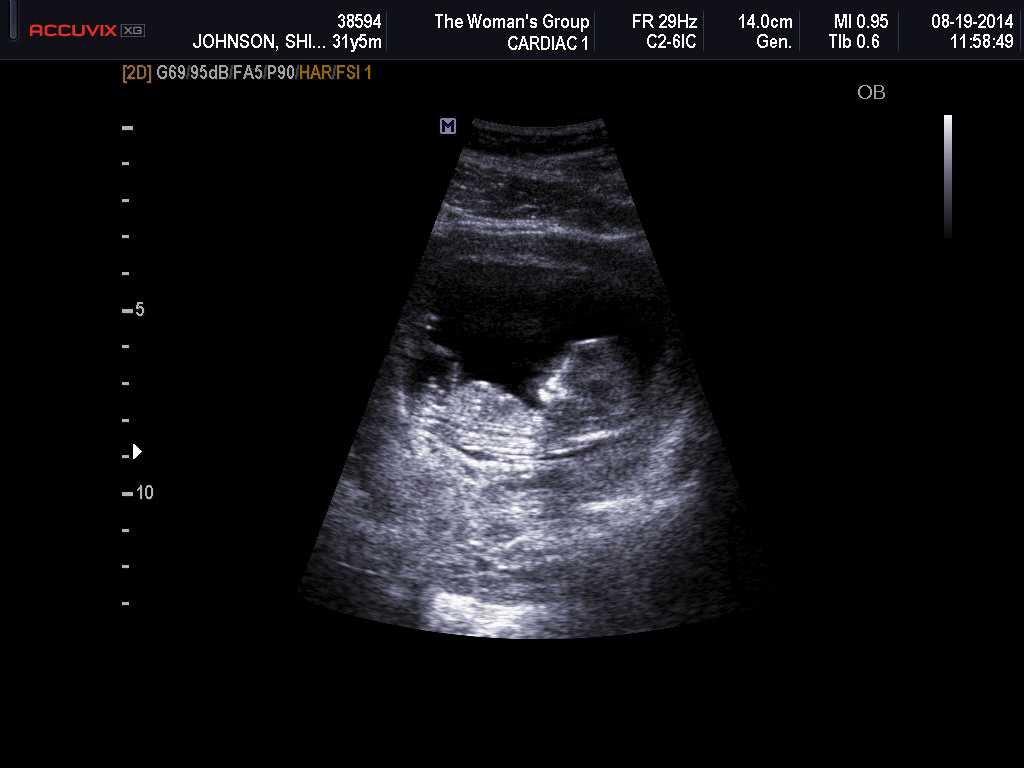

Hi ladies. We just had our first scan and baby was dating a bit ahead at 12w6d. Would love any guesses at gender :-) I have my theories, but am hoping for confirmation!! Thank you in advance!!